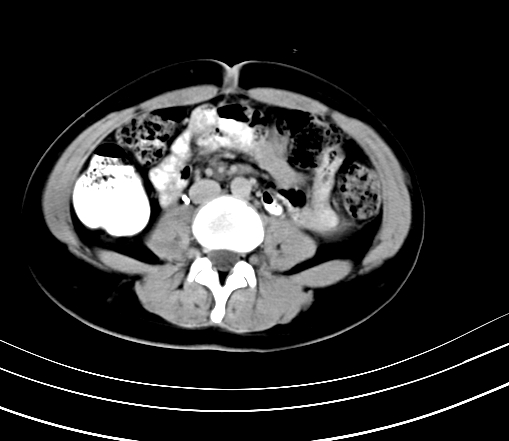

标题: CT23915:女 20岁 全身长疙瘩三年 今日多体位查 看看吧 [打印本页]

标题: CT23915:女 20岁 全身长疙瘩三年 今日多体位查 看看吧

延时5分钟

延时10分钟

神经纤维瘤病